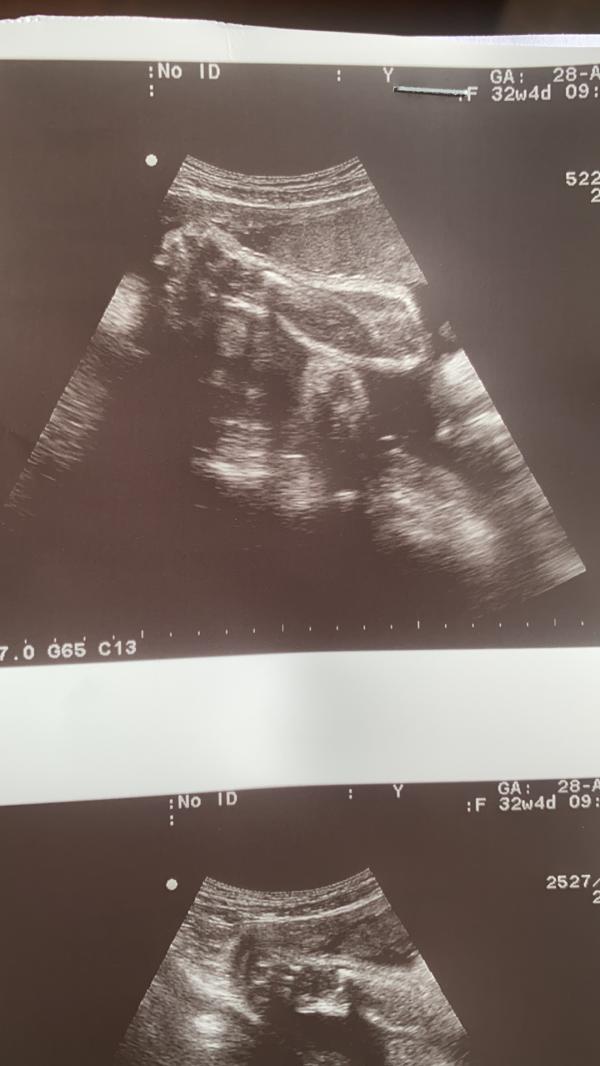

Сегодня была в платной клинике, попросила сделать узи, пересчитали показатели, развит по срокам 32-33 недели) вес 2200гр, богатырь🤩

Скромный наш мальчишка, ручками закрывал личико, кулачок показал😊 сказали волосатенький